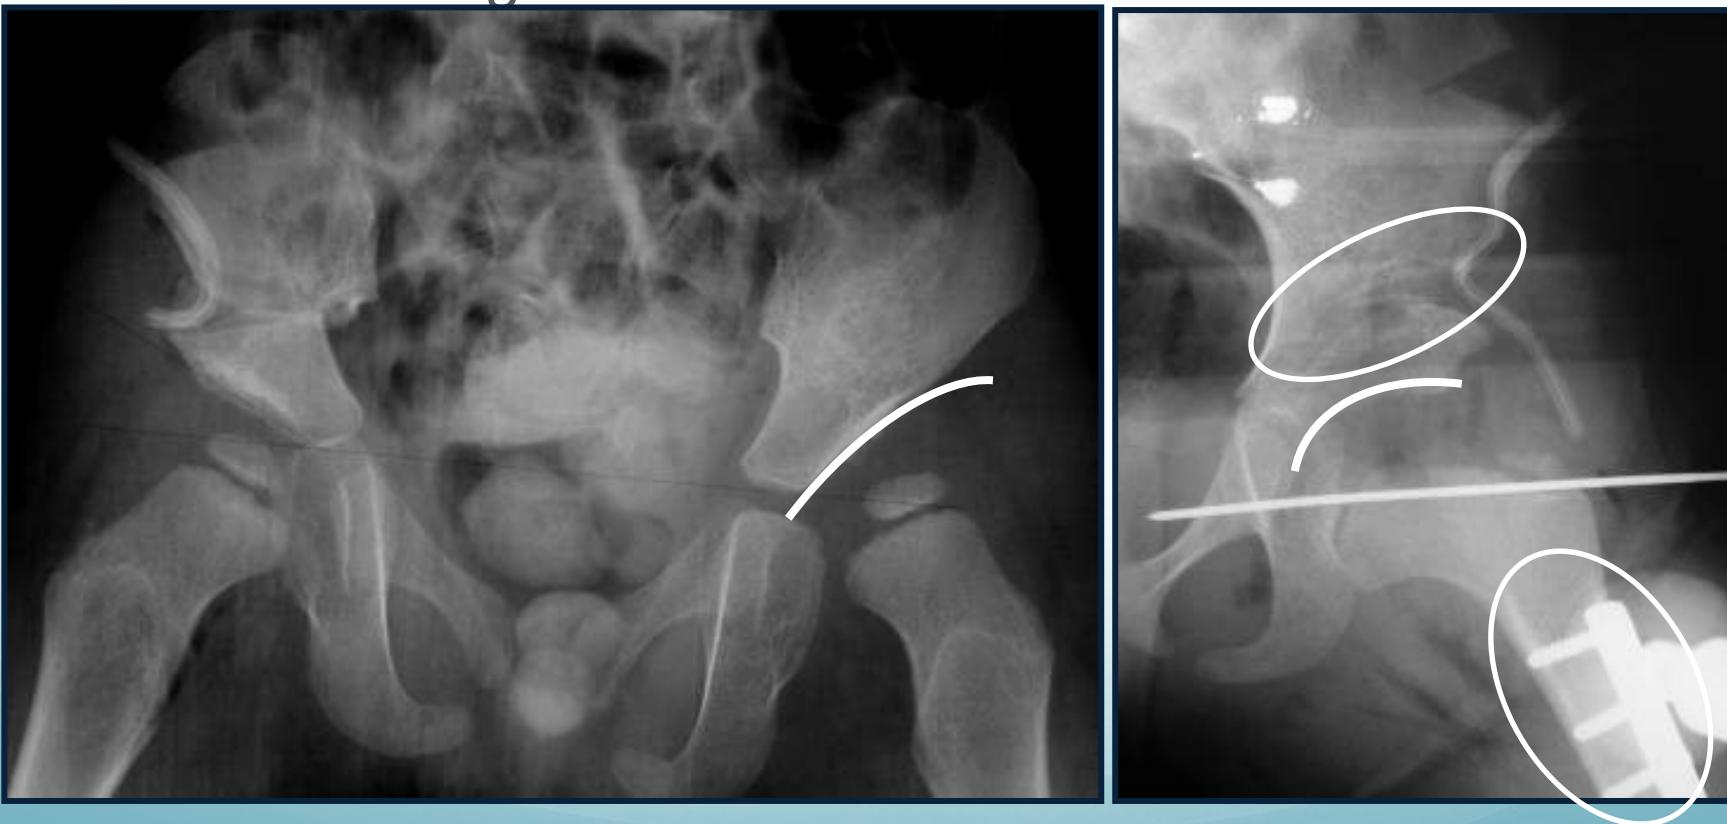

6-12 months of age

- Closed reduction & hip spica cast

- Arthrography-guided

12-24 months of age

- Surgery

- Open reduction & Acetabuloplasty (pelvic osteotomy)